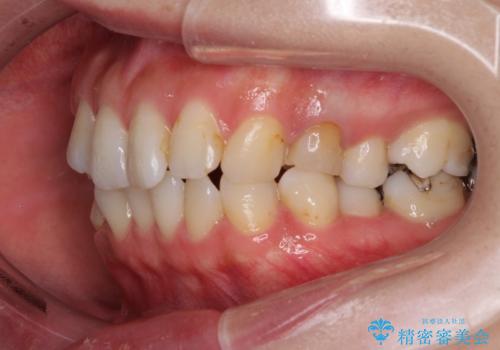

長時間のマウスピース装着と、患者様自身でのゴムかけに協力いただき、自然な口元に仕上げることができました。

気になっていた変色した歯もオールセラミッククラウンで本物の歯のようになり、患者様には大変満足していただきました。